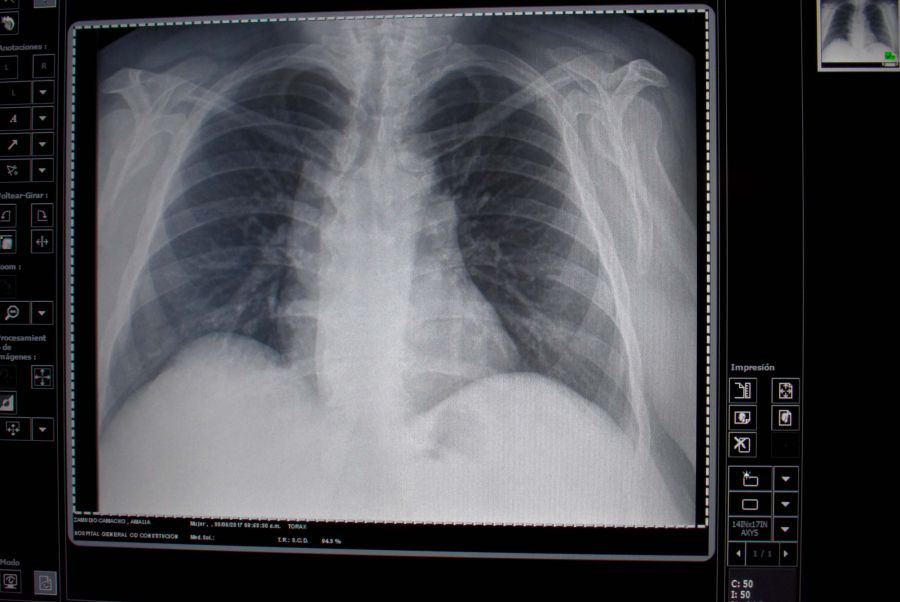

Actualmente, dijo, el método de referencia para detectar esta complicación es la tomografía, cuyo uso está limitado en etapas tempranas debido a su elevada radiación, altos costos y la poca disponibilidad de este equipo en los centros médicos periféricos o rurales.

El especialista señaló que el estudio Valor diagnóstico y predictivo del ultrasonido pulmonar en la evaluación de la enfermedad pulmonar intersticial en esclerosis sistémica, a través del cual el INR obtuvo el primer lugar de investigación clínica, propone determinar la validez de esta herramienta diagnóstica en la detección temprana de este padecimiento, una complicación común y de elevada morbi-mortalidad.